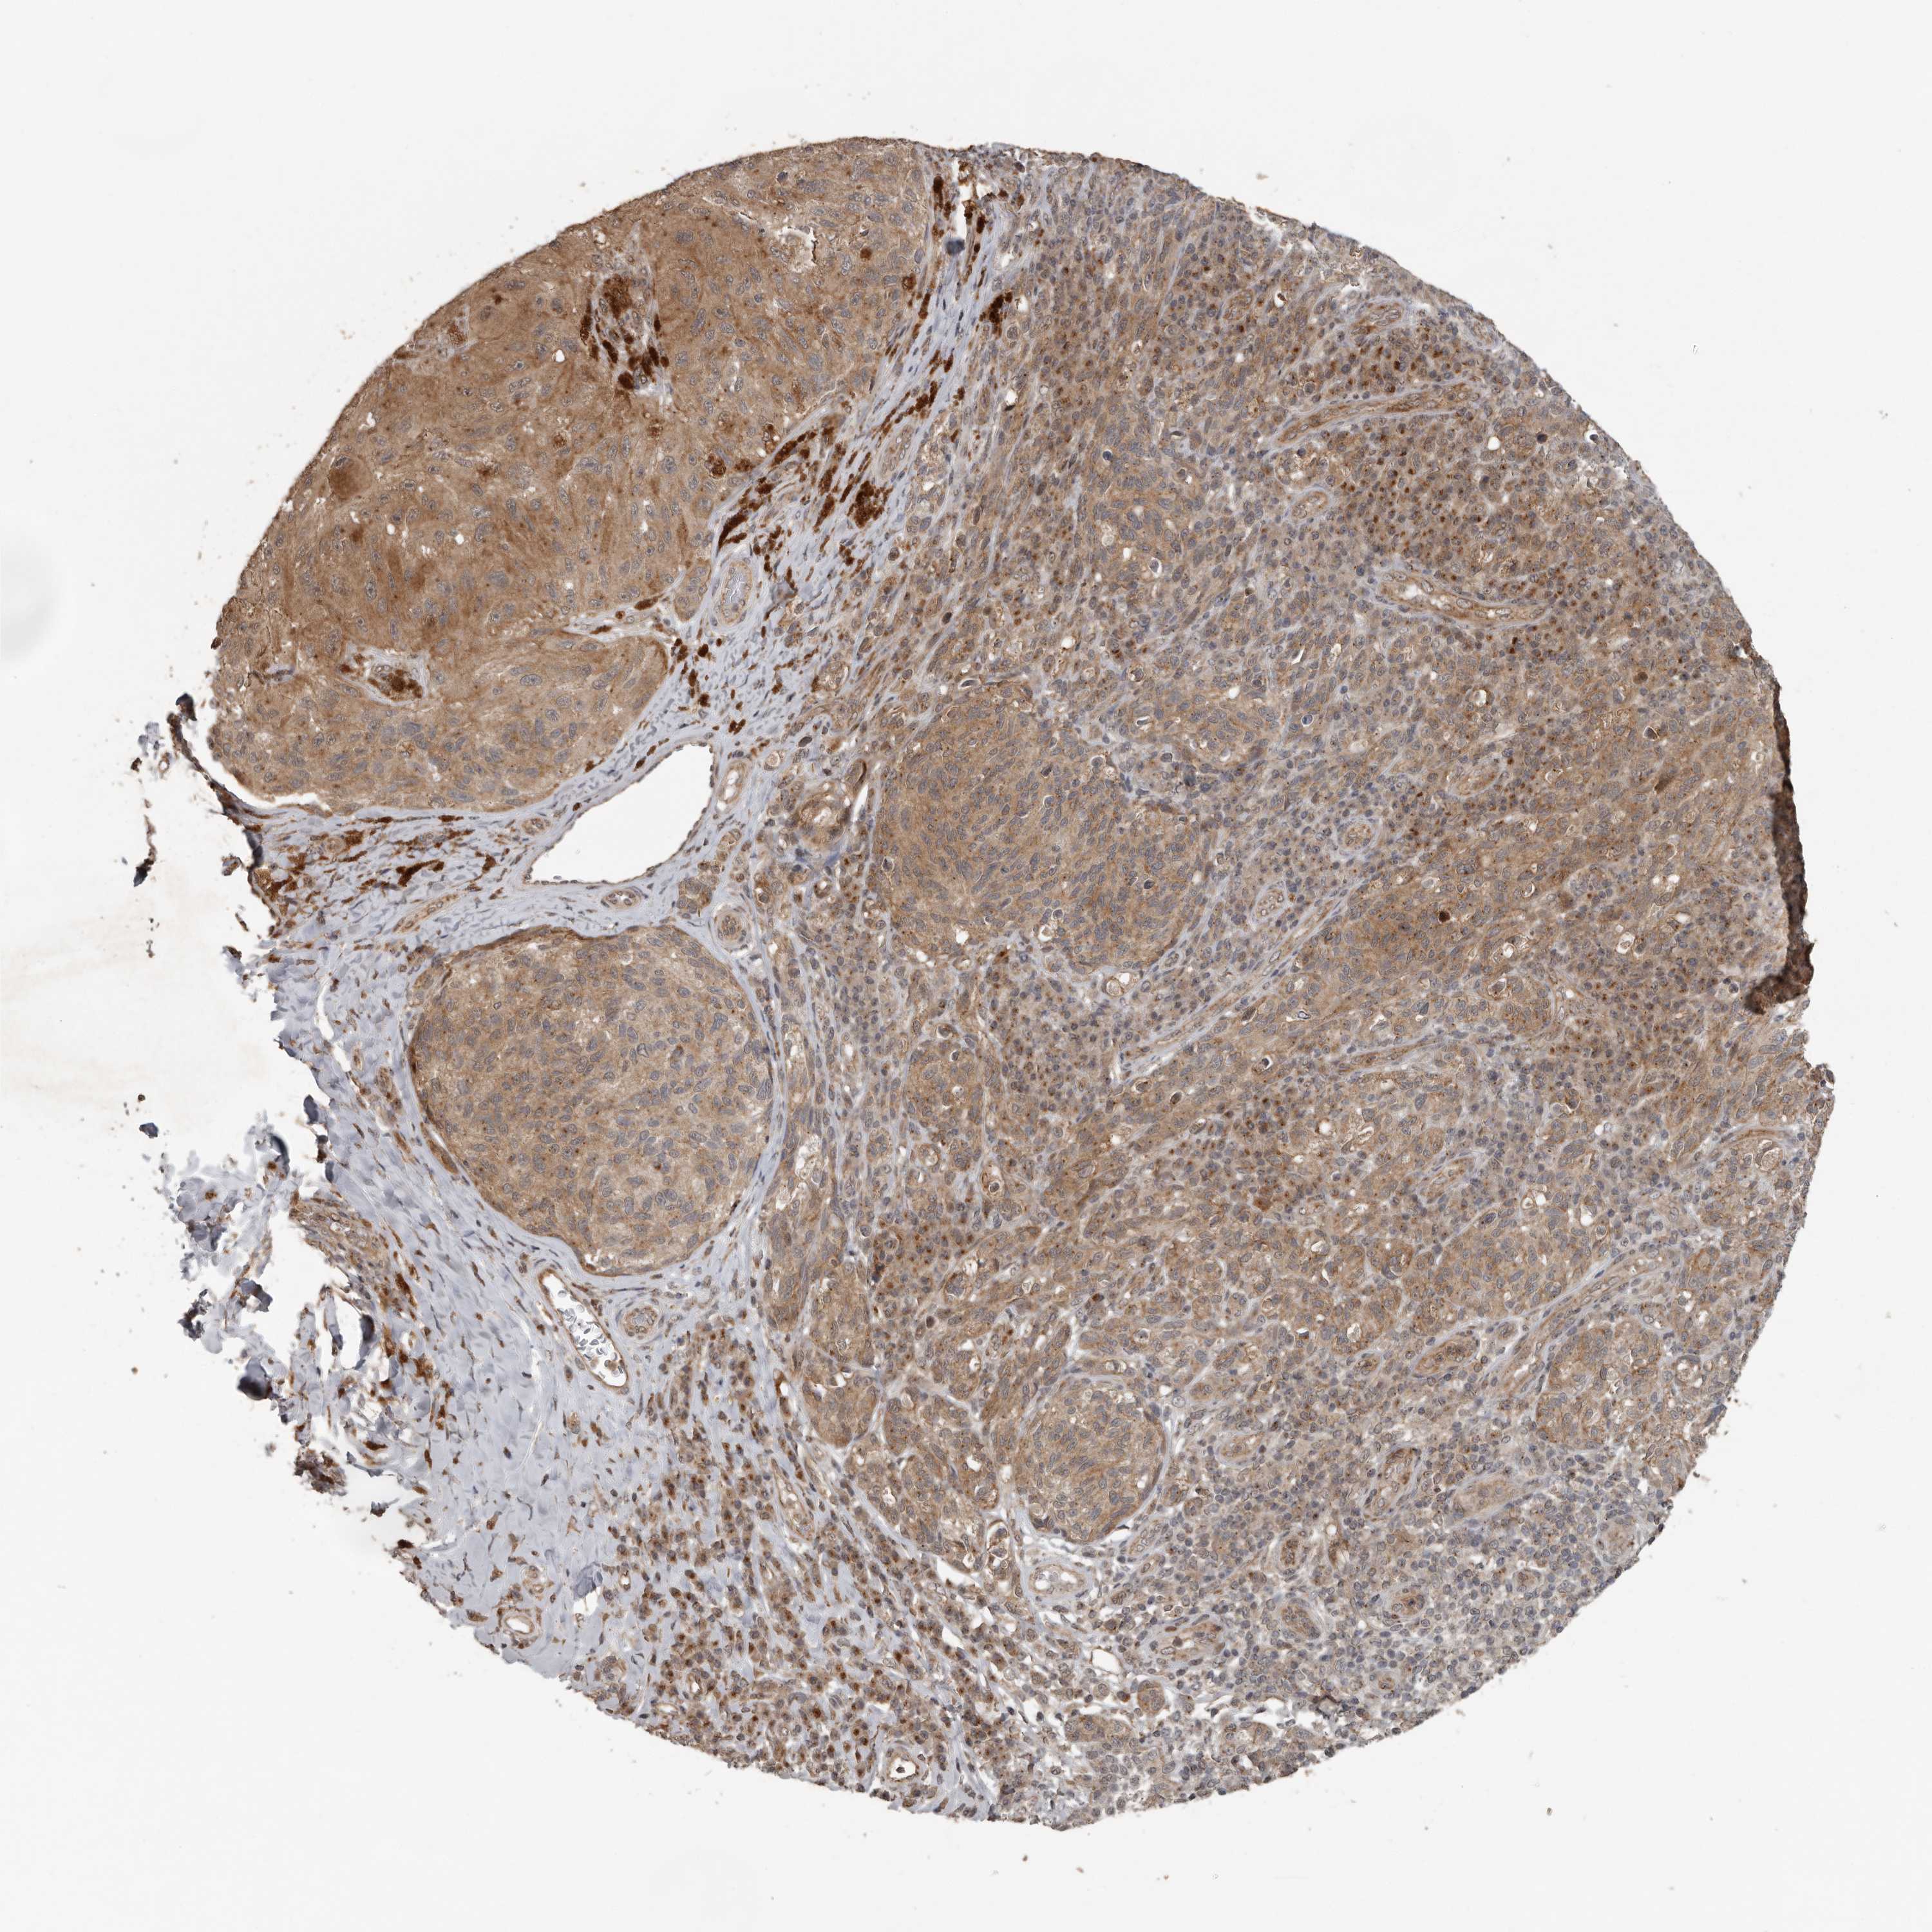

MELANOMA - Protein expressioni

A mouse-over function shows sample information and annotation data. Click on an image to view it in a full screen mode. Samples can be filtered based on level of antibody staining by selecting one or several of the following categories: high, medium, low and not detected. The assay and annotation is described here.

Note that samples used for immunohistochemistry by the Human Protein Atlas do not correspond to samples in the TCGA dataset.

Antibody stainingi

Antibody staining in the annotated cell types in the current human tissue is reported as not detected, low, medium, or high, based on conventional immunohistochemistry profiling in selected tissues. This score is based on the combination of the staining intensity and fraction of stained cells.

Each image is clickable and will lead to virtual microscopy that enables deeper exploration of all samples and also displays staining intensity scores, fraction scores and subcellular localization as well as patient and tissue information for each sample.

Antibody HPA028355

Antibody HPA028357

Staining

High

Medium

Low

Not detected

Intensity

Strong

Moderate

Weak

Negative

Quantity

>75%

75%-25%

<25%

None

Location

Nuclear

Cytoplasmic/membranous

Cytoplasmic/membranous,nuclear

Malignant melanoma, NOS

Malignant melanoma, Metastatic site